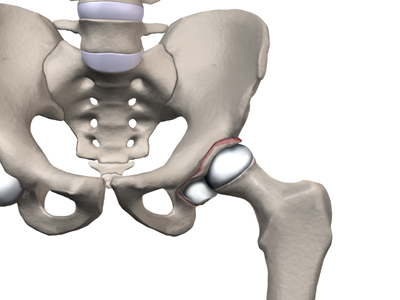

The hip joint is where the thighbone (femur) connects to the pelvis. The joint is made up of two parts. The upper end of the femur is shaped like a ball. It is called the femoral head. The femoral head fits into a socket in the pelvis called the acetabulum. This ball and socket joint is what allows us to move our leg in many directions in relation to our body.

In the growing child, there are special structures at the end of most bones called growth plates. The growth plate is sandwiched between two special areas of the bone called the epiphysis and the metaphysis. The growth plate is made of a special type of cartilage that builds bone on top of the end of the metaphysis and lengthens the bone as we grow. In the hip joint, the femoral head is one of the epiphyses of the femur.

The capital femoral epiphysis is somewhat unique. It is one of the few epiphyses in the body that is inside the joint capsule. (The joint capsule is the tissue that surrounds the joint.) The blood vessels that go to the epiphysis run along the side of the femoral neck and are in danger of being torn or pinched off if something happens to the growth plate. This can result in a loss of the blood supply to the epiphysis.